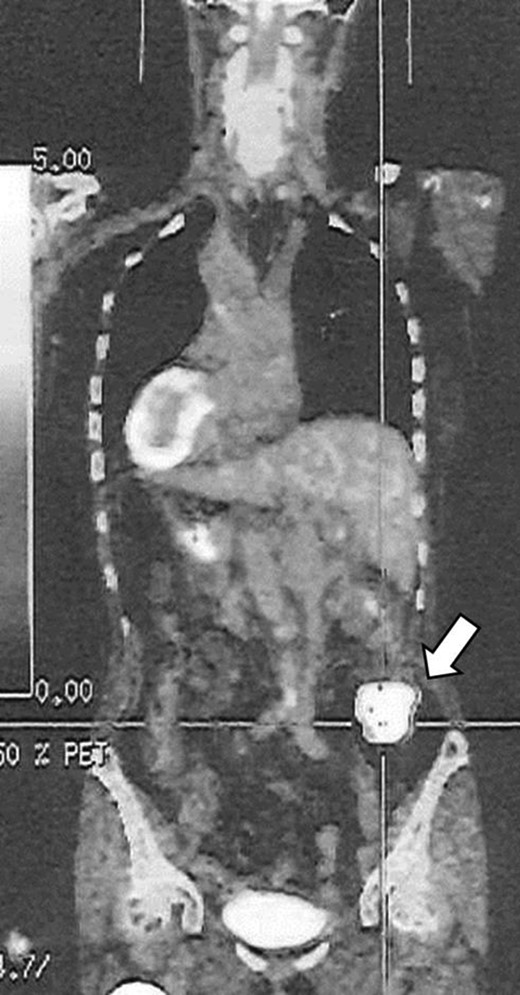

A 76-year-old woman known since early childhood to have situs inversus totalis was referred to the Breast Surgical Department for left breast cancer. She underwent F-fluorodeoxy-glucose positron emission tomography-computed tomography (FDG-PET/CT), because of high level of carcinoembryonic antigen (CEA). PET/CT image showed FDG uptake at the ascending colon (Fig. 1). Therefore, we were consulted by the doctor of Breast Surgical Department. The patient was admitted to our department for further evaluation and surgical treatment. And the treatment for the colon cancer preceded the treatment for breast cancer because of advanced stage of the colon cancer.

PET/CT image showed FDG uptake at the ascending colon (arrow).